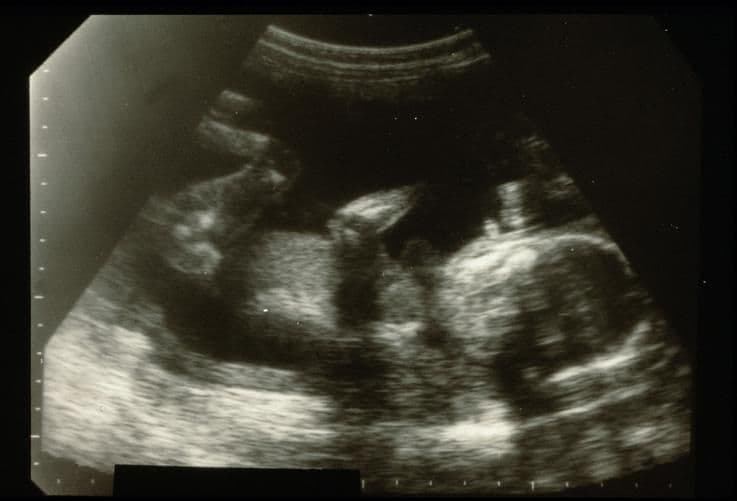

Although the baby is lying on her side and the face cannot be seen, this image does show the leg and foot particularly well. Because 2D ultrasound only shows a “slice” of the baby, parts may appear to be missing, such as the arm here which stops midway.